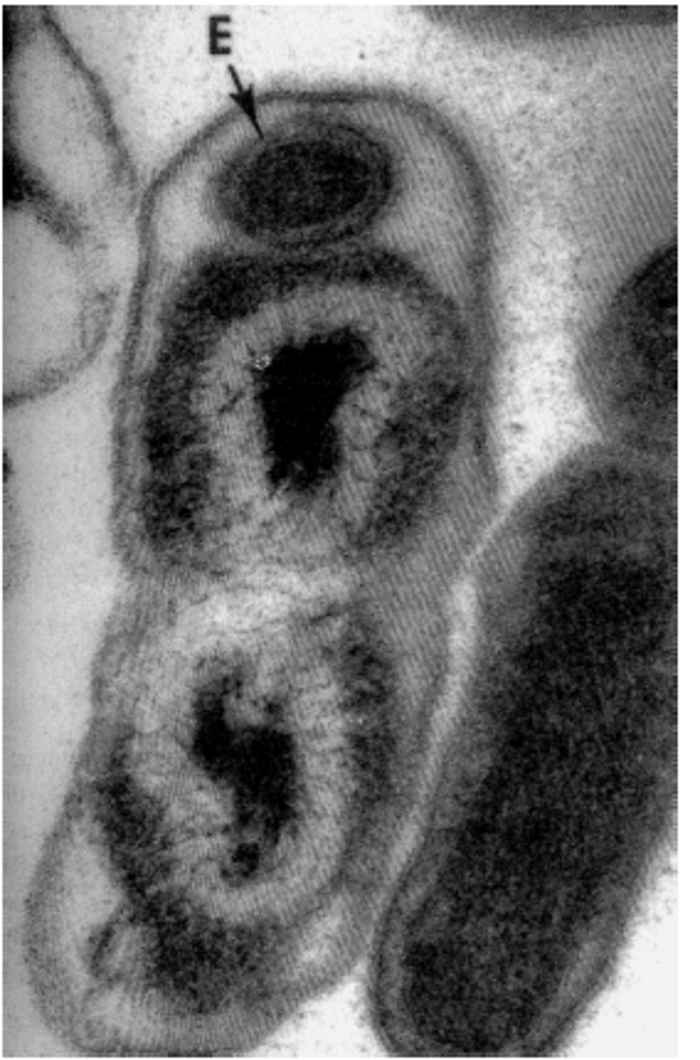

During infections, C. burnetii bind to receptors on monocytes/macrophages and are internalized in phagosomes which rapidly fuse with lysosomes to form phagolysosomes that appear as large vacuoles in infected cells.21 Coxiella burnetii is an acidophilic bacterium and its metabolism is enhanced by the acidic pH in the phagolysosome. 97 There are two distinct morphological forms of C. burnetii.53 The ‘small cell variant’ (SCV) is a compact, small rod with a very electron-dense centre of condensed nucleoid filaments while the ‘large cell variant’ (LCV) is a large, less dense, pleomorphic organism with a clear, periplasmic space between the outer and cytoplasmic membranes (Figure 43.1). A dense endospore-like body 130 to 170 nm in diameter might be found at one pole of some LCV (Figure 43.2). Both forms multiply by transverse binary fission. The SCVs are metabolically inactive and are the extracellular form of the organism. Once taken into the phagolysosome they are activated by the acidic environment and form LCVs, the metabolically active intracellular form of the bacterium. The cytoplasm of the host cell becomes filled with vacuoles loaded with organisms (Figure 43.3). ‘Large cell variants’ undergo sporogenic differentiation and form resistant, spore-like forms of the bacteria. These develop to SCVs that are released when the cells lyse.